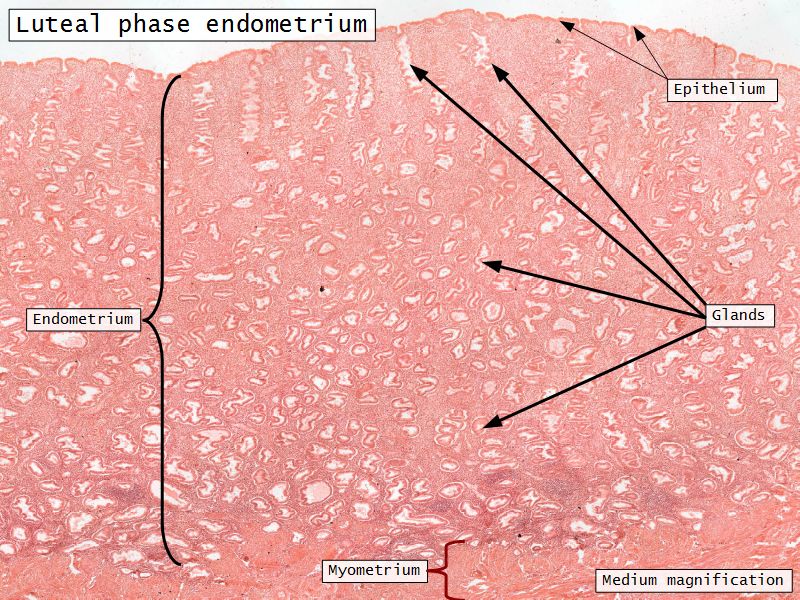

Luteal phase

- Thickening endometrium

- Edema

- Endometrial gland secretion

- Glands

- Glandular cells at apex

- Basal accumulation glycogen

- Helical arteries reach superficial regions